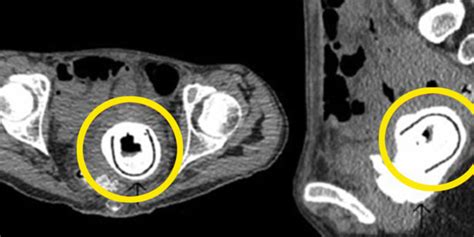

Mulher Esquece Objeto Na Vagina Por Dez Anos E Coloca Sa De Em Risco Por Que Deixamos De Ir Ao